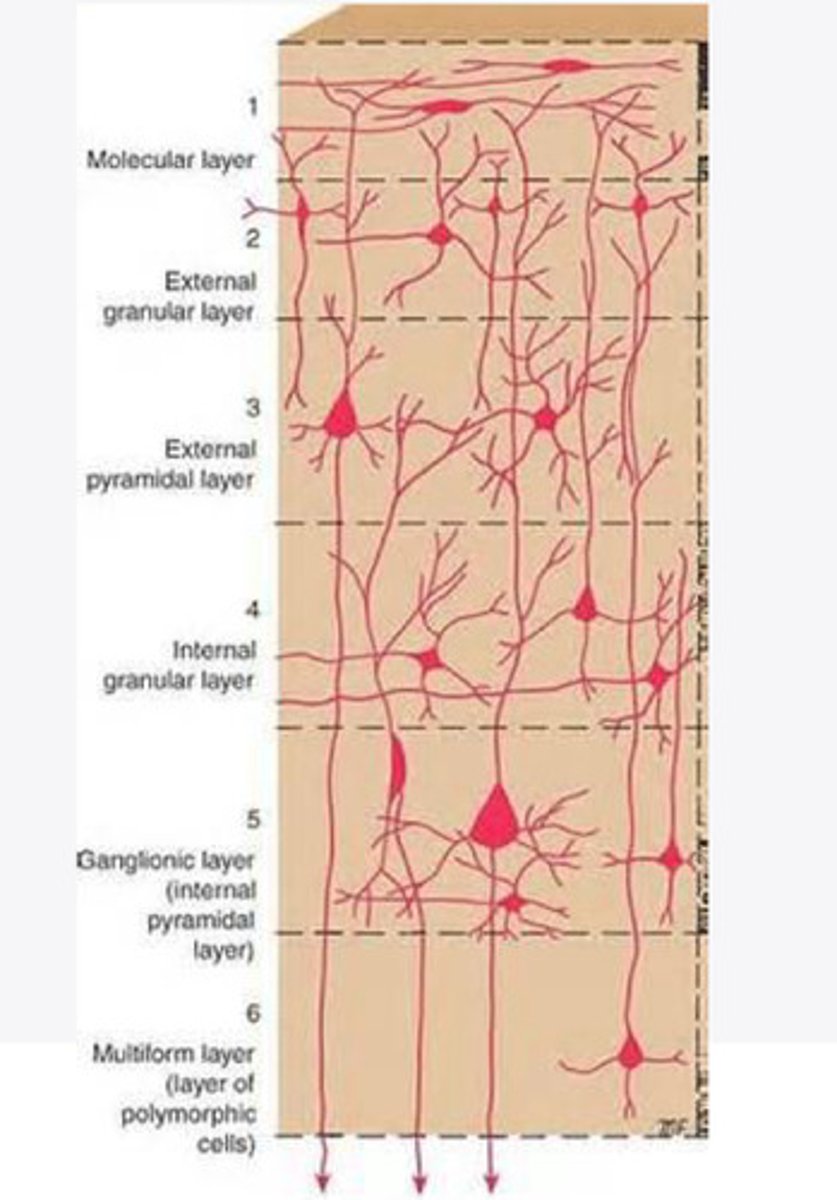

divided into 6 distinct layers, due to varying densities of cell body types within each layer

The cortex of the brain is divided into how many layers? Why is it divided into layers?

Layers of the cortex of the brain pic

2 and 4

What are the layers of the cortex that are associated with input?

3 and 5

What are the layers of the cortex that are associated with output?

molecular layer

What is the name of Layer 1 of the cortex of the brain?

very few cells

Does Layer 1 of the cortex have a lot or few cells?

receives dendrites from internal layers so it may actually function as a coordinating center where layers can communicate action

What does Layer 1 of the cortex do?

1

Every layer sends densities to Layer ____?

1

What layer serves as the "water cooler" of the brain?

external granular layer

What is the name for layer 2 of the cortex of the brain?

receives input from other cortical regions

What is the function of Layer 2 of the Cortex of the brain?

Stellate

What type of cells (stellate/pyramidal) would be most concentrated in Layer 2?

external pyramidal layer

What is the name for layer 3 of the cortex of the brain?

sends output to the other cortical layers

What is the function of Layer 3 of the cortex of the brain?

pyramidal

What type of cells (stellate/pyramidal) would be most concentrated in Layer 3 of the brain?

Layers 2 and 3

What layers are associated with association and commissural fibers?

Layer 3 - axons of cell bodies

Layer 2 - synapse into target areas in Layer 2

What part of the axons is in Layer 2/ in layer 3?

Layer 3 - external pyramidal layer

All axonal cel bodies for association and commissural fibers lie within what layer of the Cortex of the brain?

internal granular

** or called the striate cortex because it is so thick that you can see a line through this layer even in unstrained brain slides

What is the name for the 4th layer of the cortex of the brain?

receives input from the thalamus, geniculocortical layer, and other brainstem areas

What is the function for the 4th layer of the Cortex of the brain?

very thick within the vision, auditory, and somatosensory areas

Is Layer 4 thick or thin within SENSORY areas of the cortex?

Internal pyramidal

What is the name for Layer 5 of the cortex of the brain?

sends axons to the brainstem (corticobulbar) and spinal cord (corticospinal)

What is the function of Layer 5 of the cortex of the brain?

in motor areas of the cortex?

Where is layer 5 very thick in the brain?

the frontal lobe -- very motor heavy

What lobe of the brain will have a thick layer 5 of the cortex of the brain?

the multiform layer

What is the name of layer 6 of the cortex of the brain?

-sends axons back to the thalamus through corticogeniculate fibers

-modulates what information the thalamus sends to the cortex to control the strength of the signal received and modulate what you pay attention to

What is the function of layer 6 of the cortex of the brain?

no

Is layer 6 a motor layer?